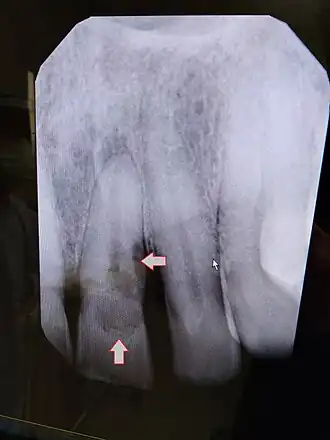

![]() | |

| Post traumatic External tooth resorption 9 | |

| Diagnostic method | Dental examination, X-rays |

External resorption is the loss of tooth structure from the external surface of the tooth and is further subcategorized based on its etiology.[16]

External inflammatory root resorption may be caused by trauma to the root surface, due to damage to the periodontal ligament (PDL) and/or extended drying following tooth avulsion. Following trauma, dentinal tubules are exposed leading to communication with an infective or necrotic pulp. This leads to an inflammatory process that causes external root resorption.[16]